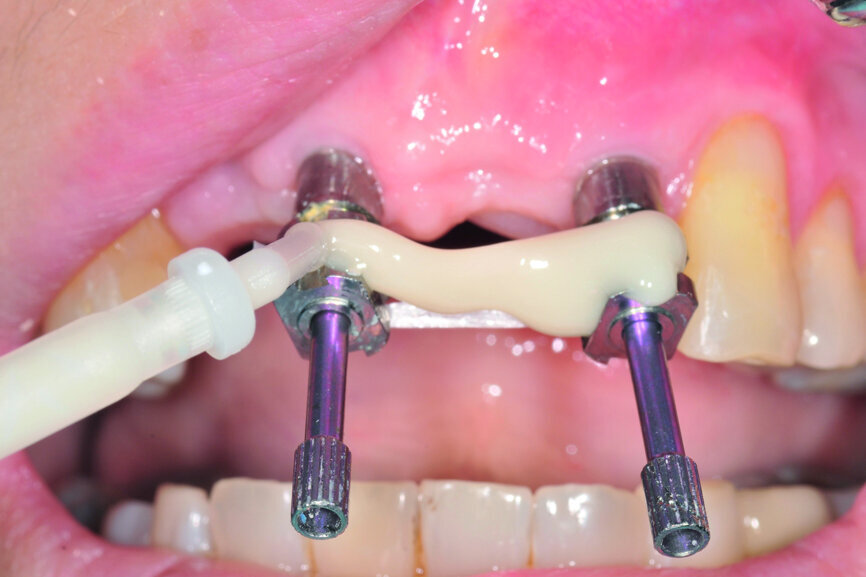

Fig. 12: Two impression copings connected for the implant level impression.

Teeth #12, 21 and 22 were extracted. Tooth #11 underwent early implantation and tooth #22 immediate implantation with GBR (Figs. 5 & 6). After three months of healing, osseointegration had taken place. An implant level impression was taken for fabricating a provisional bridge supported by temporary abutments for teeth #12–22. The technician modified the shape of the artificial gingiva on the model in order to form the proper gingival curve and emergence profile, then finished the provisional bridge, while the dentist modified the gingival shape using an olive-shaped bur intraorally (Figs. 7–18).

Once the aesthetic and functional outcomes had been confirmed, the anterior guidance of the provisional restoration was recorded on an articulator (Artex, Amann Girrbach) and its individual incisal guide table (Figs. 24–27). Next, the emergence profile of the provisional restoration was transferred and the cast model was made and mounted on the articulator (Figs. 28–33).